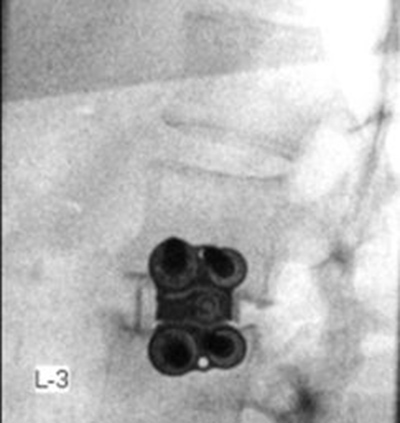

Extreme lateral interbody fusion (XLIF) is a minimally invasive surgical procedure performed from a lateral approach to remove a diseased disk with placement of an artificial disk and performance of lateral fixation with plate and screws going into the vertebral bodies above and below the diseased disk space level (Nuvasive) (Ha, 2014; Petscavage-Thomas, 2020) (figure: XLIF). A similar procedure is the transforaminal lumbar interbody fusion (TLIF).